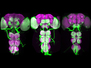

In a stunning phenomenon called ‘blindsight’, people who are blind in one eye can respond to visual stimuli they can’t consciously see at all. They might, for example, be able to grab an object to their side, only in the line of ‘sight’ of their blind eye. To investigate, researchers scanned the brains of healthy volunteers (left) and a patient with damage to one side of the brain (right). They found that the intact side compensates for, and communicates with, the injured. When the patient responded to stimuli they could actually see to one side, the corresponding half of the brain was active. However, when they responded to ‘hidden’ stimuli, both sides of the brain were involved, as were the fibres connecting them (the corpus callosum, blue and larger in the injured brain). Understanding these inbuilt compensation and repair mechanisms could help us encourage recovery after brain injury.